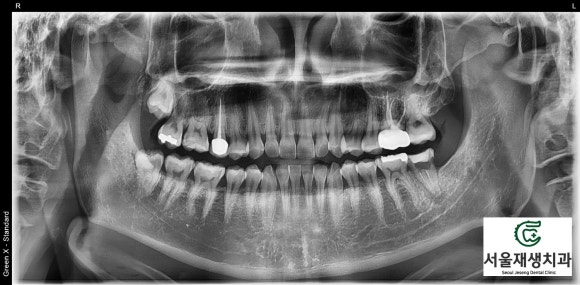

뿌리 측면에 녹아있던 뼈가 재생되었습니다.

불과 치료 두 달만의 일입니다.